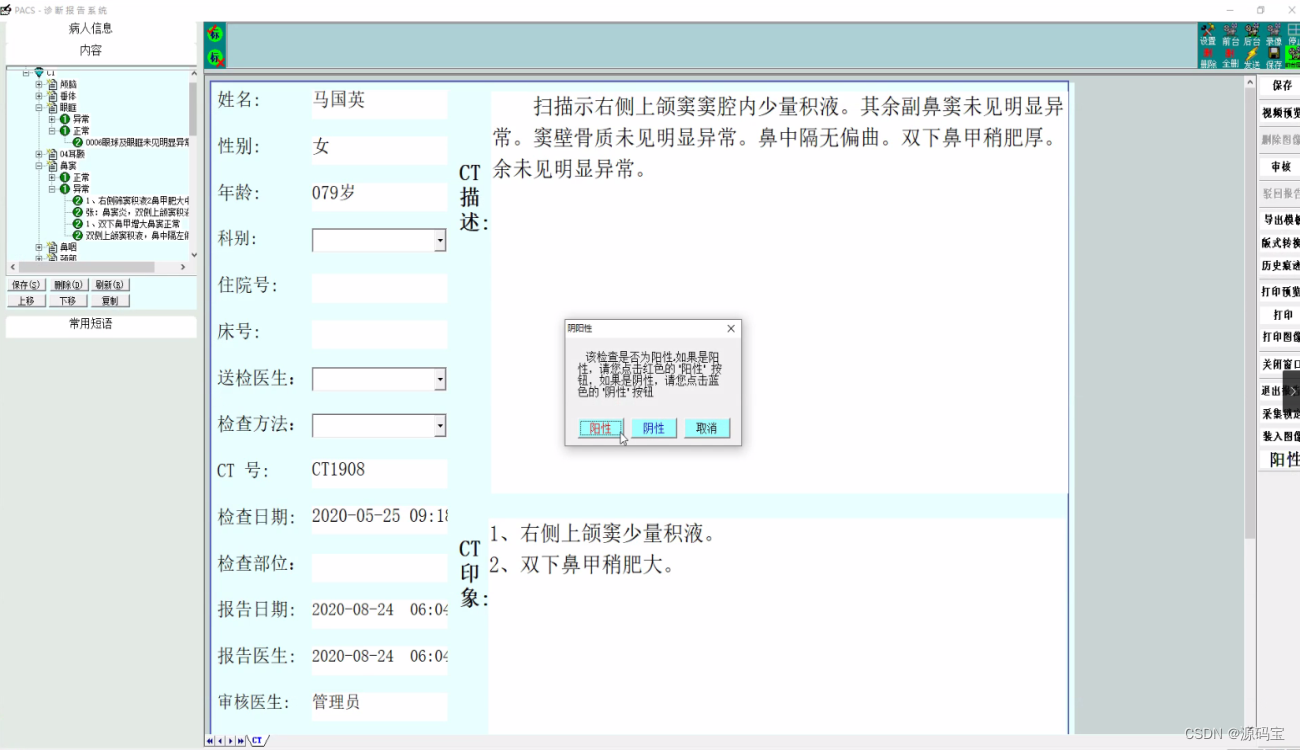

(4)分析诊断报告

提供专业丰富的诊断模板,并可以由医生添加、修改、删除,并可设置使用权限,可设置成医生独用或公用;

支持自定义报告样式,支持图文混排;

报告支持多级医生审核,支持典型病例管理;

报告所见即所得,支持报告打印自动缩放。